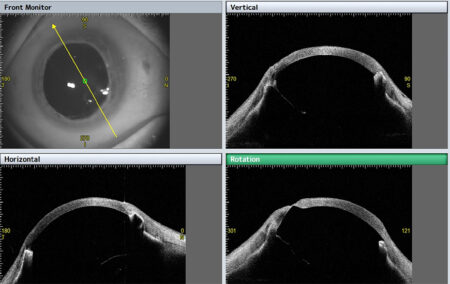

- Analiza kąta przesączania w 360°,

W aplikacji STAR 360°, CASIA2, dzięki automatycznemu wykrywaniu ostrogi twardówki mierzy kąt przesaczania na pełnym obwodzie przedniego segmentu, co zapewnia szczegółowe parametry umożliwiające perfekcyjną diagnostykę jaskry.

Nie tylko mierzy, ale także wyświetla wynik na szczegółowym wykresie/mapie graficznej. Wykresy można wybierać spośród wszystkich wartości pomiarowych w zależności od własnych potrzeb.